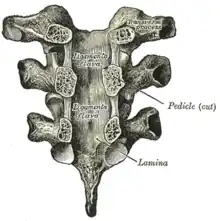

Pédicule de l'arc vertébral

Les pédicules sont dirigés vers l'arrière et légèrement vers le haut.

Les encoches vertébrales inférieures sont de grande taille et plus profondes que dans toute autre région de la colonne vertébrale.

Lame de l'arc vertébral

Les lames sont larges, épaisses et imbriquées – c'est-à-dire qu'elles chevauchent celles des vertèbres sous-jacentes comme des tuiles sur un toit et se connectent avec les pédicules pour entourer et protéger la moelle épinière.